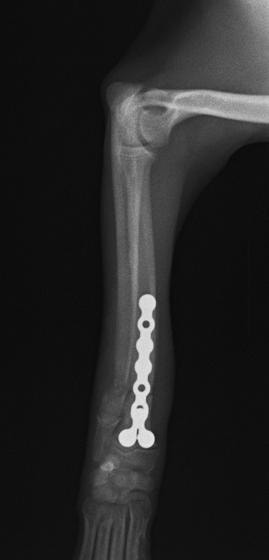

ペルシャ猫 11ヶ月齢 雄

他院にて左大腿骨遠位の成長板骨折(salter-harrisⅠ型)が認められており、治療相談を目的として来院。当院にて、キルシュナーワイヤーを用いたピンニングにより骨折部位の整復を行いました。術後の経過は良好で、現在も経過観察中です。

術後レントゲン

機器

Arthrex社のターゲティングデバイスを用いてピンニングの位置を調整することで、確実な固定を行っています。当院ではこの手術器具以外にも、人の手術にも使用される様々な器具を導入し、手術精度を高め、また医療メーカーと新しい器具の開発、試作にも取り組んでおります。